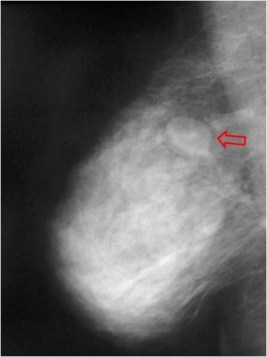

SIGNO DEL HALO EN LA MAMA

La buena delimitación de las lesiones mamarias en la mamografía, rodeadas de un fino halo hipodenso, fue erróneamente considerada durante mucho tiempo como signo de benignidad.

En este caso, la ecografía confirma que se trata de una lesión quística. Pero también algunas lesiones sólidas, tanto benignas como malignas, pueden presentar este signo.

El interés de mostrarlo es para insistir en su inespecificidad.

Puedes consultar en artículo de Cupples TE, Eklund GW y Cardeñosa G. Mammographic halo sign revisited. Radiology 1996; 199:105-108.